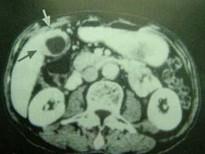

问题 女,58岁,上腹部疼痛半月,无畏寒、发热、黄疸等症状,CT检查如图,最可能的诊断是 ( )

选项 A、胆囊息肉 B、胆囊转移瘤 C、胆囊癌(胆囊壁增厚型) D、胆囊腺肌增生症 E、慢性胆囊炎

答案 C